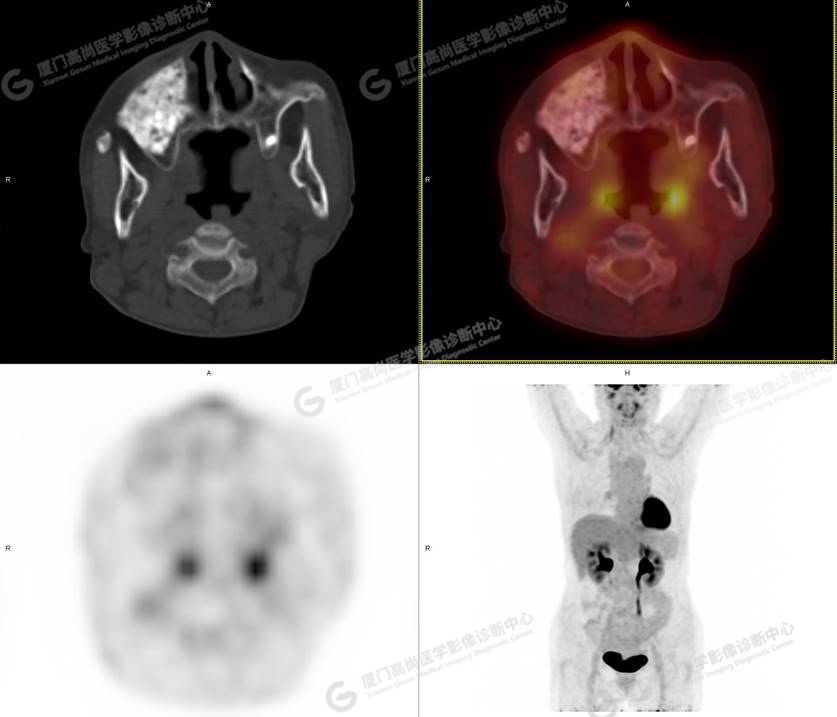

圖1

圖2

圖3

圖4

PET/CT所見:右側(cè)上頜骨、右側(cè)顴骨及右側(cè)額骨骨質(zhì)膨脹,其內(nèi)密度不均勻性增高,部分放射性攝取輕微增高,SUVmax 2.27。